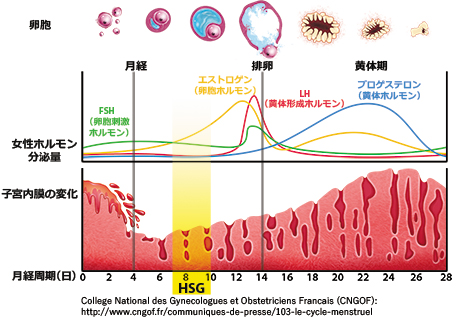

リピオドール®を使用した子宮卵管造影(HSG)の準備

1)不妊・不育症診療パーフェクトガイド, 臨婦産. 2016; 70(4): p.68. 医学書院

2)高橋俊文. 臨婦産. 2019; 73(11): 1144-1152. より改変